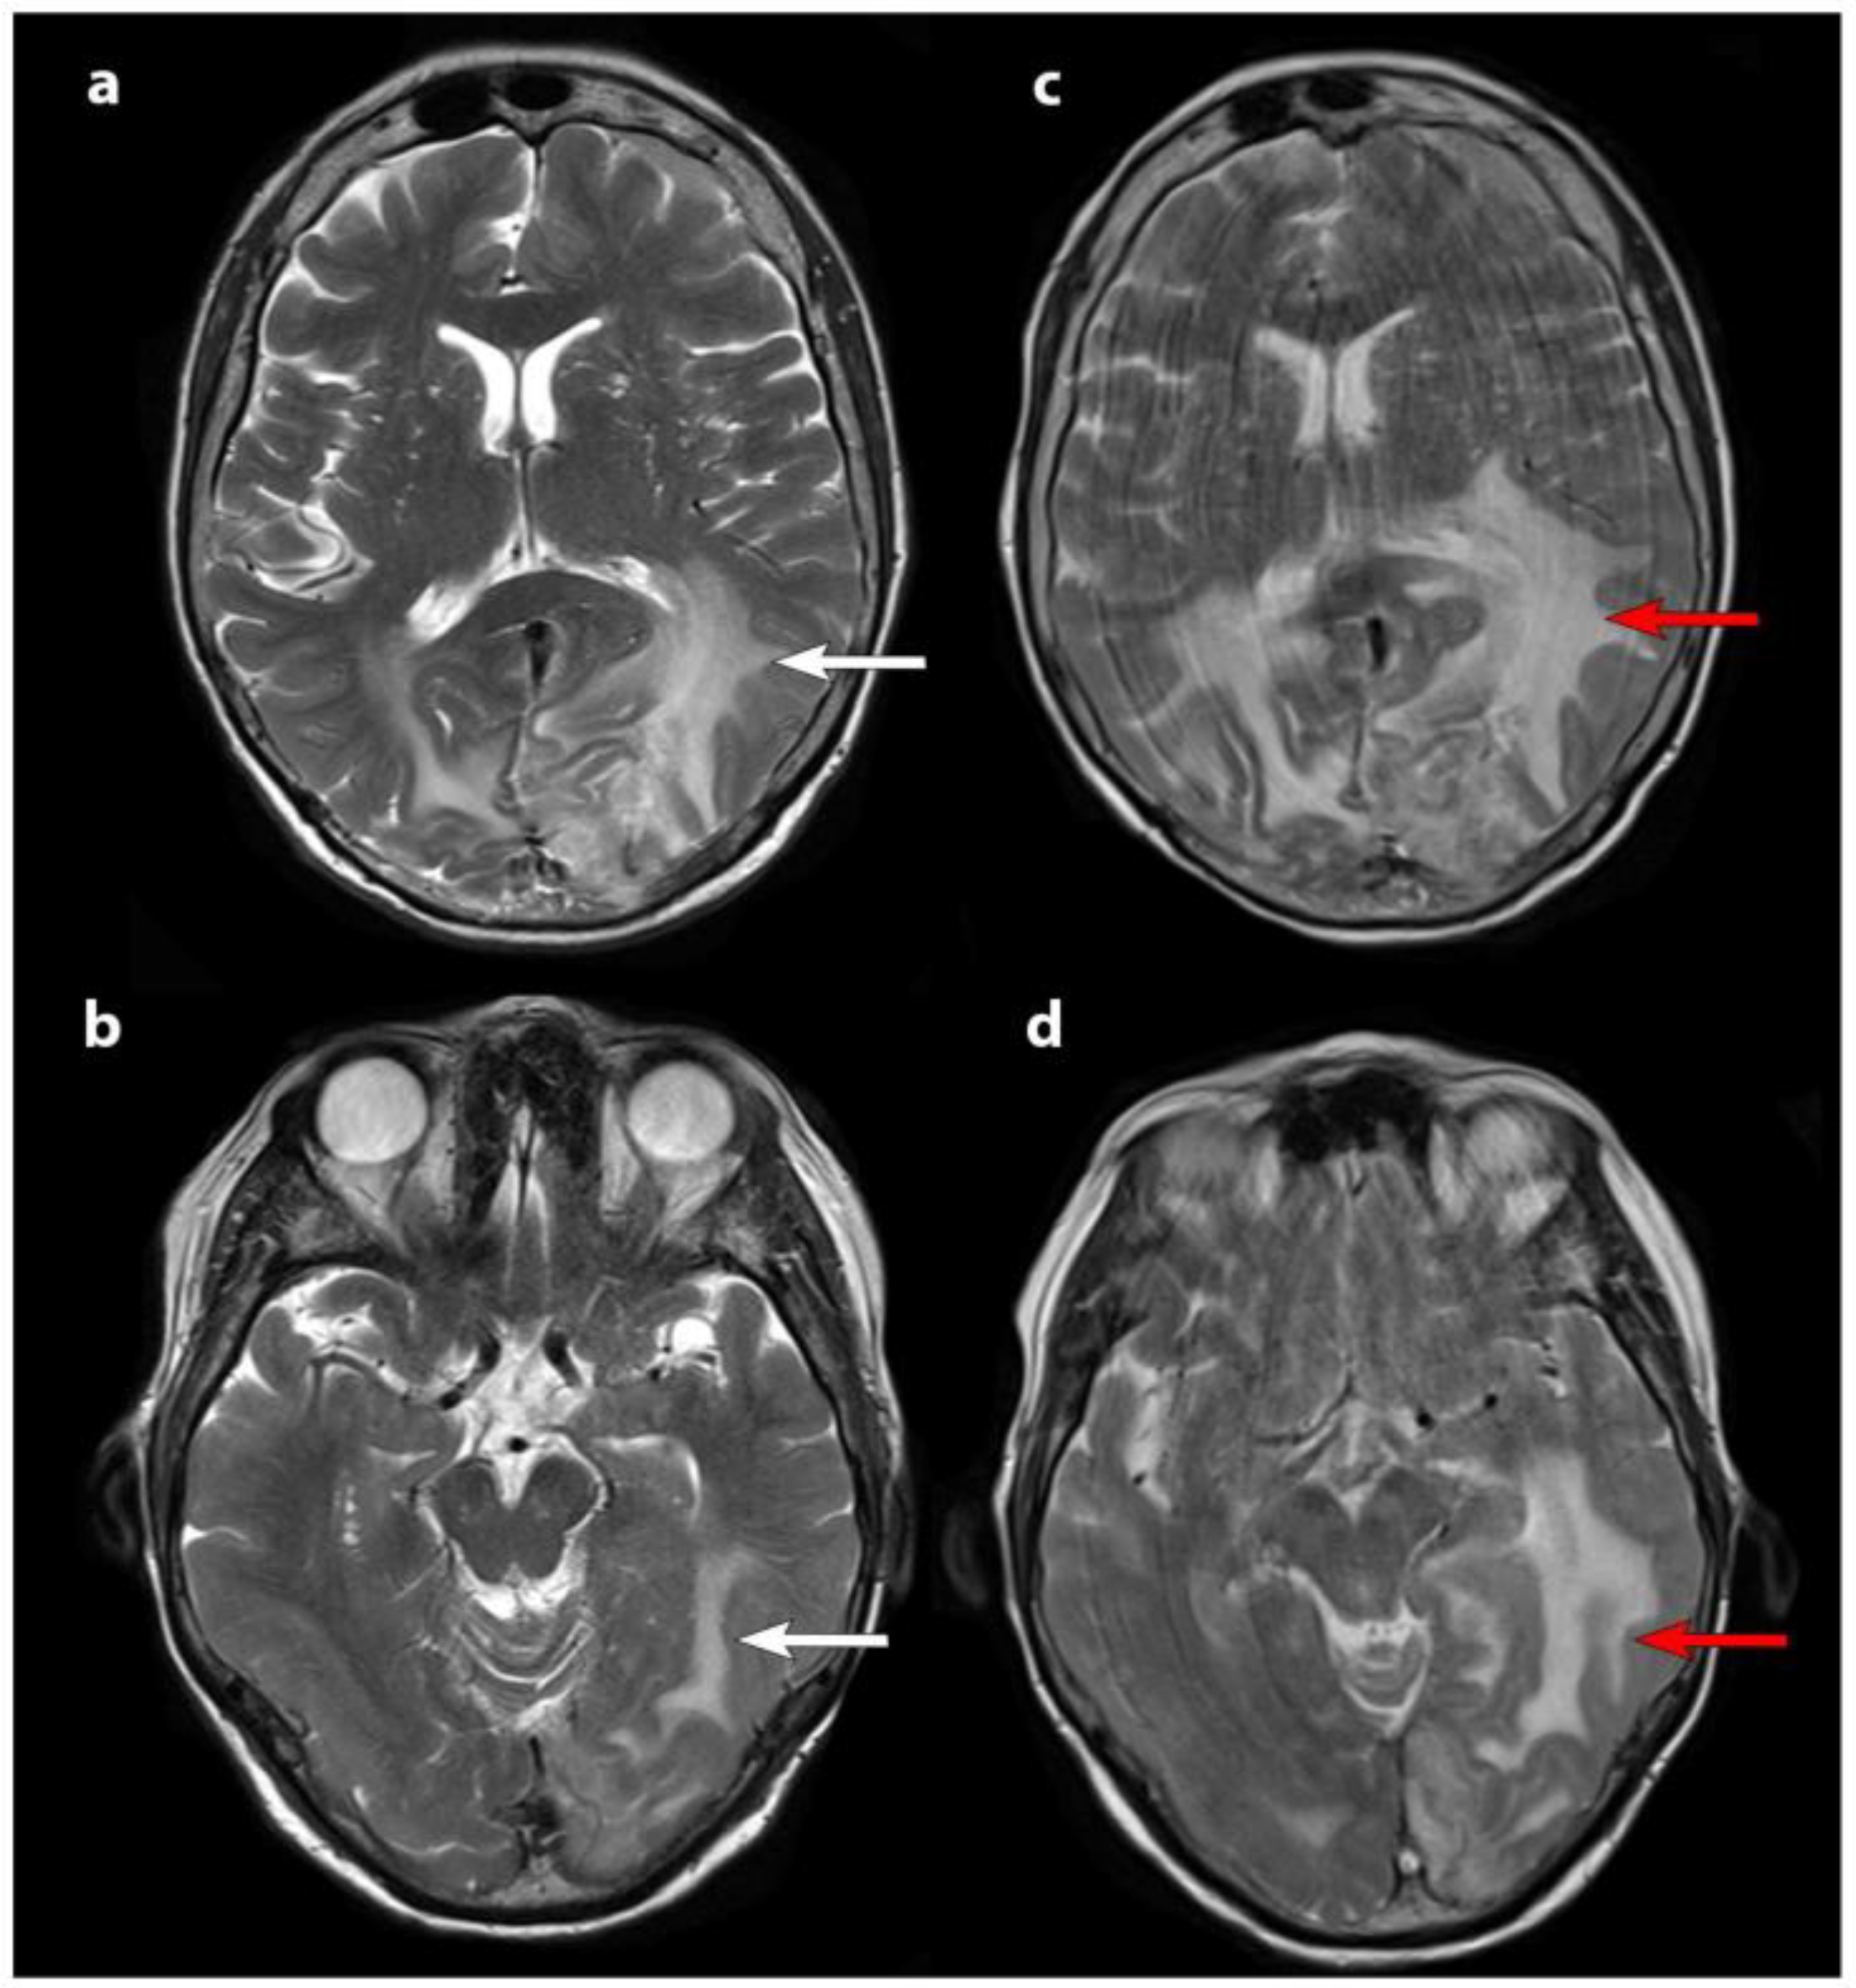

- Lütgendorf-Caucig, C.; Pelak, M.; Flechl, B.; Georg, P.; Fossati, P.; Stock, M.; Traub-Weidinger, T.; Marosi, C.; Haberler, C.; Zechmeister-Machhart, G.; et al. The trends and significance of SSTR PET/CT added to MRI in follow-up imaging of low-grade meningioma treated with fractionated proton therapy. Strahlenther. Onkol. 2023, 199, 396–403. [Google Scholar] [CrossRef] [PubMed]

| Grade I (WHO) | 22 | 68Ga-DOTATOC PET/CT | 81.8% showed reduced SUVmean/TLA post-treatment; increased heterogeneity index in 75%. | [36] | |